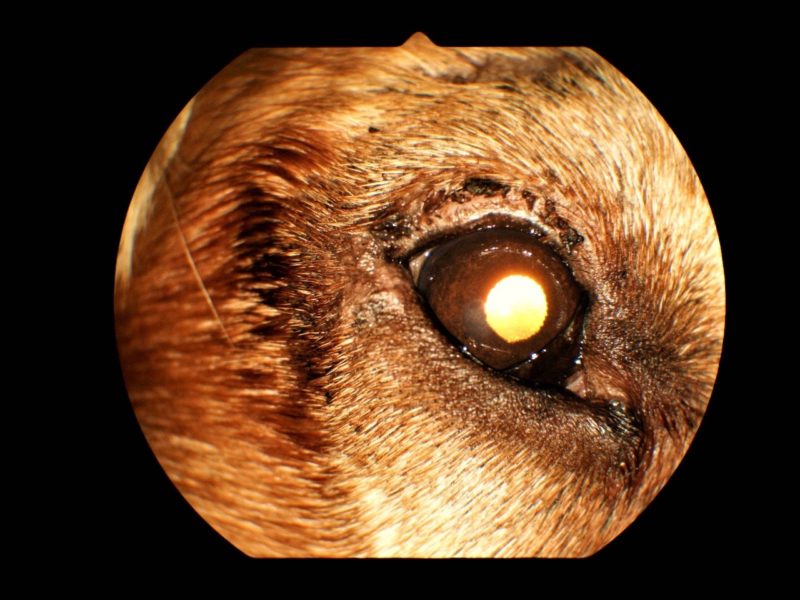

Diese Operationsmethode verstärkt zum einen den gewünschten Lifting-Effekt und zum anderen verhindert es bei fortschreitender Bindegewebsschwäche (was mit fortschreitendem Alter durchaus vorkommen kann) eine erneute Reizung des Auges durch die wimpernartigen Haare (Abb. 3).